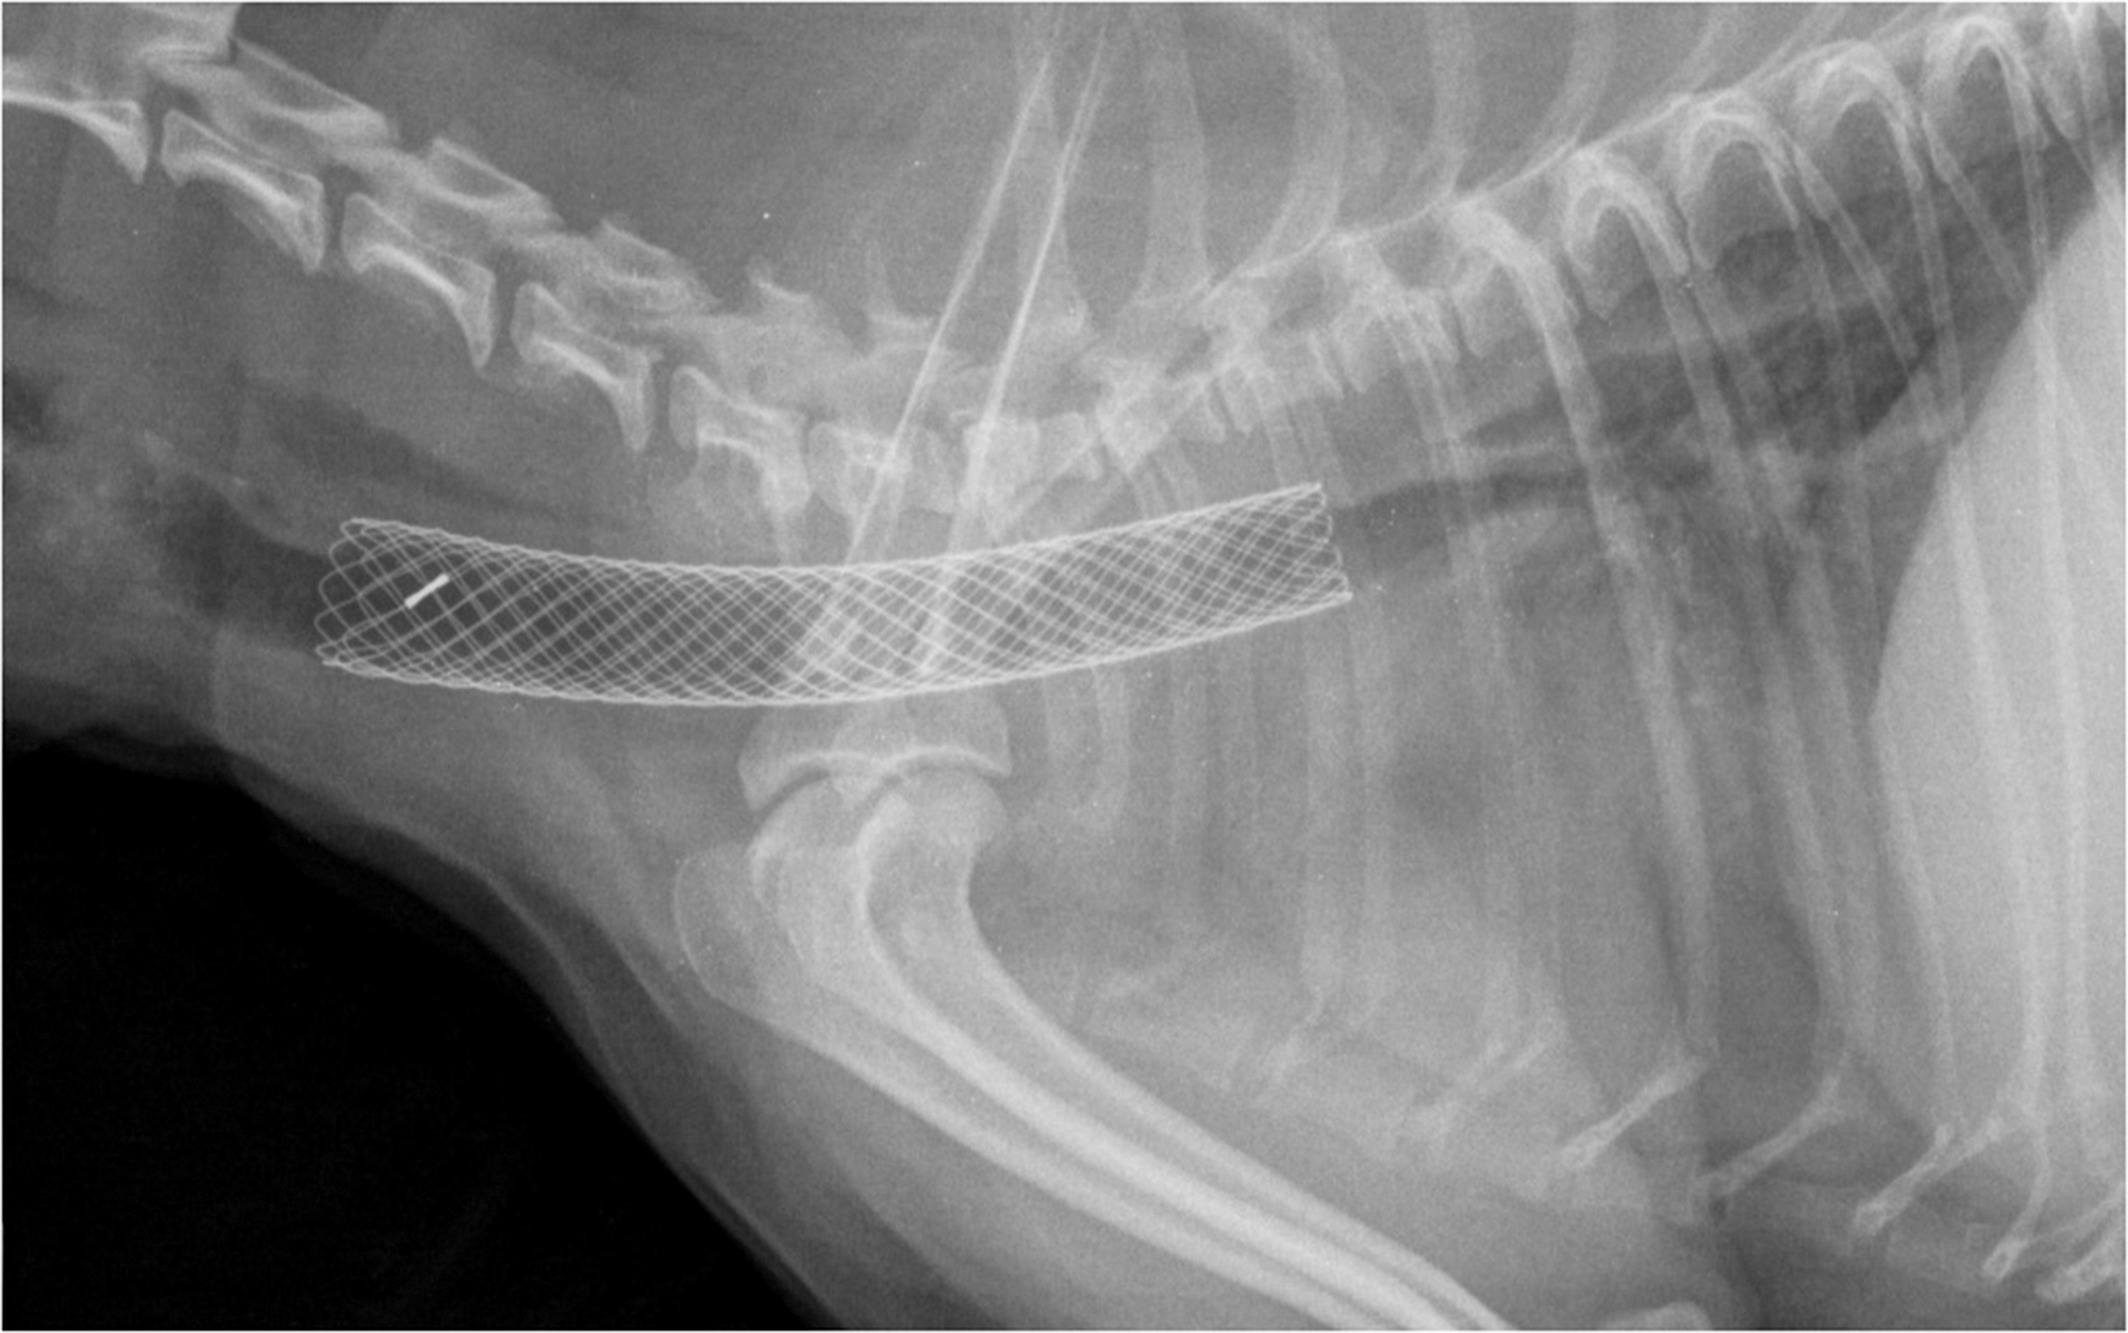

Коллапс трахеи кашель

Коллапс трахеи кашель 117 фото